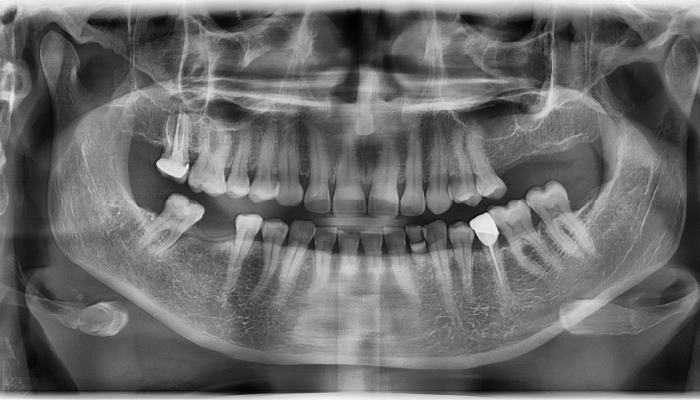

• 식립 전

식립 후